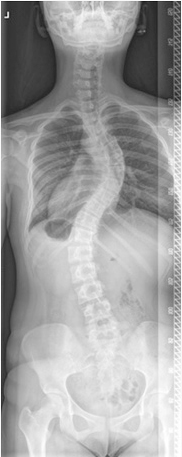

좌우로 생긴 척추 변형을 측만증이라 부르며, 확실한 원인이 밝혀지지 않은 10도 이상 척추체의 회전이 동반된 척추 측만증을 특발성 척추 측만증이라 정의하며, 종양이나 염증, 신경학적 질환, 근육 질환, 중추 신경 이상, 척수 이상 등으로 인한 측만증을 제외한 후에야 진단 내릴 수 있는 병명입니다. 특발성 측만증은 측만증의 가장 흔한 형태로 전체 측만증의 85%를 차지합니다. 분류는 여러 방법이 있으나, 치료나 임상 양상을 고려해 볼 때 발견 시기를 기준으로 유아기형, 연소기형, 청소년기형, 성인기형 등으로 구분할 수 있으며, 이중 가장 흔한 경우가 청소년기형입니다.

증례